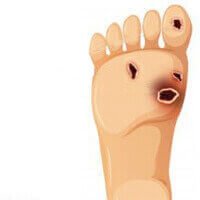

- Oksidatif stresi azaltır, iltihaplanmayı azaltır, böbrek fibrozisiyle savaşır

Piyasadaki çoğu antidiyabet ürünü sadece belirtileri yok ediyor, sorunun sebebini değil. Dianon diyabet kontrolünde mükemmel, sürdürülebilir bir etki sağlıyor. Bir kür sonrasında diyabet giderek yok oluyor, tüm vücut fonksiyonları geri kazanılıyor bozukluklar ve metabolizma bozuklukları tamamen düzeliyor.